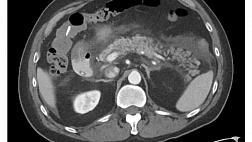

Рисунок 10. Эндоскопическая картина основных изменений после неудачной фундопликации. [13]

А. Нормальная фундопликация; B. сеточная эрозия; С. Частично разрушенная фундопликация; D. Почти полностью разрушенная фундопликация; E. Рецидивная грыжа пищеводного отверстия диафрагмы с внутригрудной фундопликацией; F. Смещенная фундопликация; G. Скрученная фундопликация; H. Двухкамерный желудок; I. Частично разрушенная фундопликация при рецидиве параэзофагеальной грыжи; J. Фундопликация со смещением (J/1:антеградная проекция; J/2: ретрофлексная проекция)